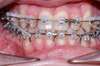

Intra Orale Droite